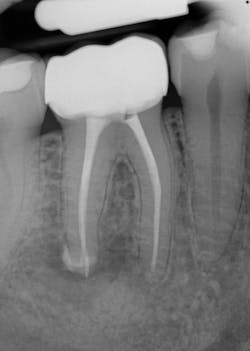

Various clinical presentations and risk factors can influence endodontic success or failure, including but not limited to the quality of the root canal performed and the seal of the coronal restoration.2 In addition to the aforementioned factors, the presence and size of a periapical lesion can directly affect the prognosis and treatment outcome. Classic literature highlights this shift in long-term success rates from 96% for vital/nonvital cases without the presence of a periapical lesion to 86% when a periapical lesion is present.3

Periapical radiographs have been commonly used to evaluate the size of periapical lesions. However, periapical radiographs have limitations, because the information is rendered in only two dimensions. A periapical lesion can only be detected in the radiograph when the mineral loss of bone reaches 30%–50%.4